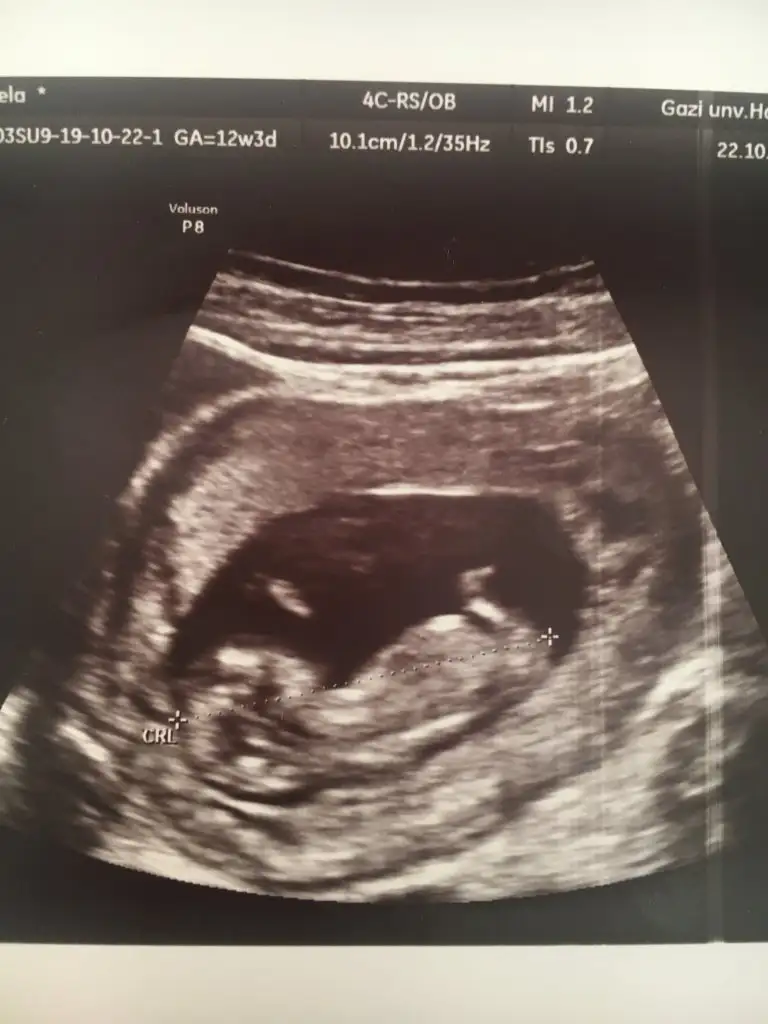

Nub görememiştim kafa yapısı erkek demiştim. tutmaya bilir demişimKızlar doktorum bir türlü emin olamıyor çıldıracağımkıza benziyor ama kıyafet alma dedi, bir daha bakın şuna lütfeen 12 hafta 1 günlük burda